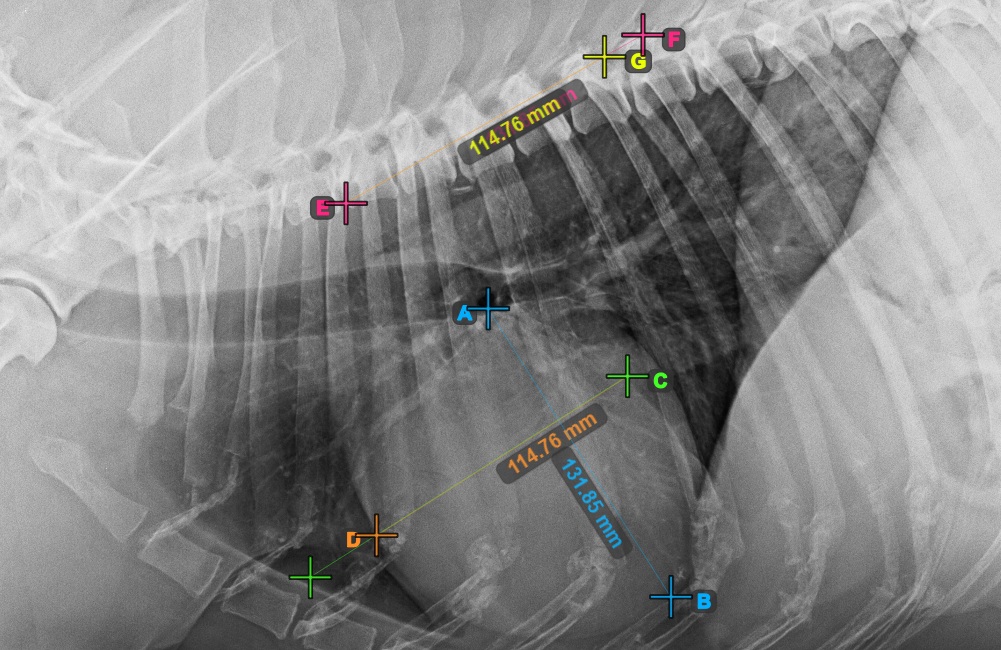

Start the measurement by marking the Bifurcatio tracheae, near the top of the heart.

The image below represents a typical placement of the Bifurcatio tracheae point.

Complete the long axis of the heart by marking the Apex point, near the bottom of the heart.

The image below represents a typical placement of the Apex point.

Continue the measurement by marking the widest right (cranial) point of the short axis of the heart.

The image below represents a typical placement of the most cranial point on the short axis of the heart.

Complete the short axis of the heart by marking the widest left (caudal) point.

The image below represents the typical placement of the most caudal point on the short axis of the heart.